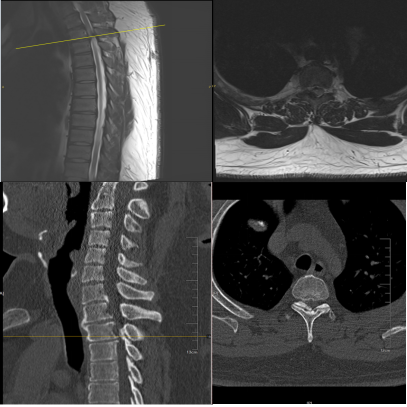

来自上海的32岁的王先生,身高196cm,体重160kg,BMI高达41.6(正常BMI一般在18.5-23.9),是一位名副其实的“巨人”。尽管身形魁梧,王先生却是一位优秀的长号手,毕业于音乐学院,拥有不少跟随他学习乐器的学生。然而,近一个多月王先生感到双下肢麻木。两周前症状迅速加重,双下肢的乏力、行走不稳,只能拄拐行走,不得不暂停授课。听闻姜为民主任的医术了得,王先生慕名前来就诊。CT及MR检查结果显示,王先生上胸椎T2-3水平黄韧带骨化伴严重的胸椎管狭窄。

术后复查胸椎CT显示,患者体内骨化块已完全切除,脊髓充分减压。考虑到患者体重较重且下肢肌力较弱,医生建议他暂缓下床行走。王先生下肢乏力的症状相较于术前已经有了明显的改善,他的脸上也露出了久违的笑容。术后仅4天,王先生便顺利出院,返回上海进一步休养。